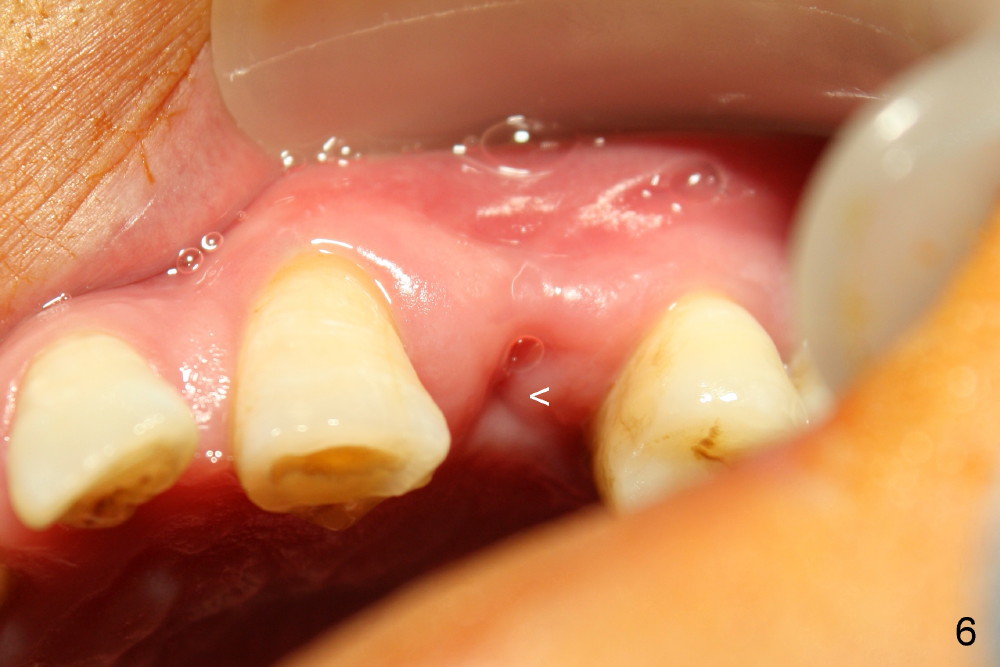

Dear Drs. Dunson and Borgner: Thank you for support. Fig.5 and 6 taken immediately prior to surgery show that the healing socket is elliptical (arrowhead). After D1 and D2 channel formers, D2 thin socket former is tapped in (Fig.7). The osteotomy needs to be redirected as shown by the black line. D2 implant is being inserted with Synthograft applied to the 1st two threads (Fig.8) and is in place (Fig.9,10). But the implant is not as stable as expected. There is a gap mesial to the implant (Fig.10 arrowhead), which is most likely created by re-directing the osteotomy with channel and socket formers.